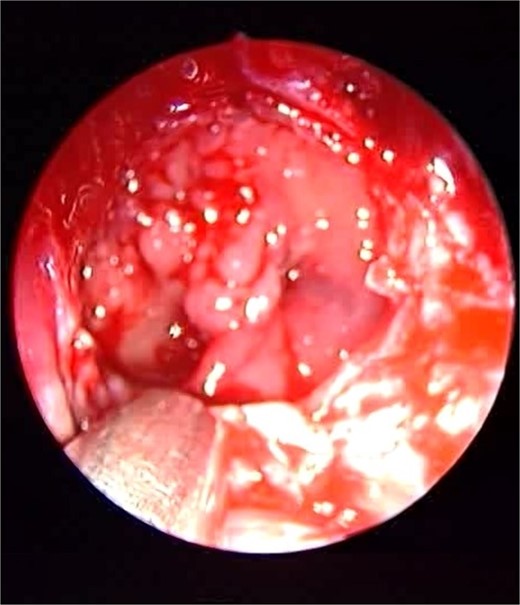

Endoscopic intraoperative image of the sphenoid sinus post removal of the fungal mud and mucin from the lateral wall of the sphenoid sinus.

Patient presented to the emergency department with four days history of sever left side headache associated with nausea and vomiting, and nasal discharge with on\off nasal obstruction. Two days history of diplopia with lateral gaze of the left eye, with decrease the visual acuity. Ophthalmologic examination revealed left abducens nerve palsy. Other neurologic examinations were within normal. Endoscopic nasal examination revealed left multiple grade two nasal polyps occupying the middle meatus. Pre-operative brain computed tomography (CT) shows bilateral near total opacification and expansion of the paranasal sinuses and nasal cavity (Fig. 1). Additionally, there is evidence of invasion of the left cavernous sinus with encasement of cavernous segment of left internal carotid artery (ICA). Furthermore, pituitary gland and optic chiasm displaced superiorly. Magnetic resonance imaging revealed that the sphenoid sinus is expanded and bulging superiorly into the pituitary fossa causing displacement of pituitary gland and stalk without mass effect upon the optic chiasm (Fig. 2). It extends laterally causing effacement of the cavernous sinus and left Meckel’s cave. No evidence of intracranial extension. The patient underwent functional endoscopic sinus surgery with computer-assisted navigation system. Intraoperatively, sphenoid sinus was full of fungal mud and mucin (Fig. 3). The polyps were removed completely from the nasal cavities, fungal mud, and mucin were removed from the sinuses (Figs 4 and 5). Patient had dramatic improvement after surgery, the rhinosinusitis symptoms are resolved, the diplopia has been improved, and the paranasal sinuses were clear. The patient was discharged with topical corticosteroid and saline irrigations.